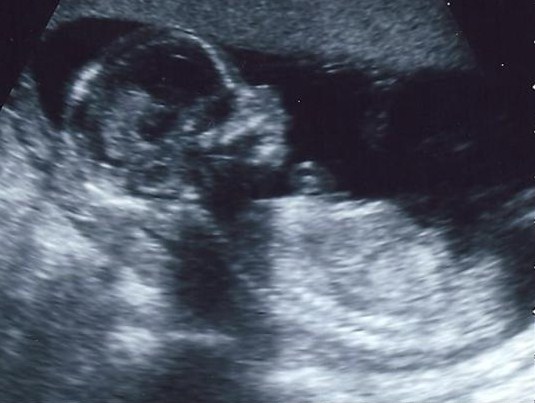

I am now in my second trimester! Woohoo!! So excited to finally be in this stage and have high hopes that my nausea will dissipate soon! We went to the doctor's a couple weeks ago and of course, don't really know how things are going because I won't get result of anything until my next appointment in a couple more weeks. One interesting thing though, I was about 12 1/2 weeks when we went, but my doctor thought I was much further along than that: at LEAST 14 weeks, he said. I think that's impossible considering I pretty much know for a fact we didn't get pregnant any sooner than we actually did. Anyway, I'm trying not to speculate too much because I don't want to get my hopes up for something that may not happen. Oh, we did hear the heartbeat!! It was such a wonderful experience, but as soon as the doctor found it he took the doppler away, so we only heard maybe 4 or 5 beats. We have our first ultrasound on the 15th and I will be over 16 weeks then, so I desperately hope they can tell if it's a boy or a girl!! I just want to really start focusing on names and start buying things that are gender specific! Oh yeah, I got full Medi-cal coverage for the pregnancy, which is such a lifesaver! It only worries me that Bryan may go out of state for law school and then we just may be stuck again so we'll see what happens. Speaking of Bryan and law school, so far he has been accepted to Gonzaga University and the University of LaVerne!! I'm so proud of him!! So that's our update, hope you enjoyed it!!